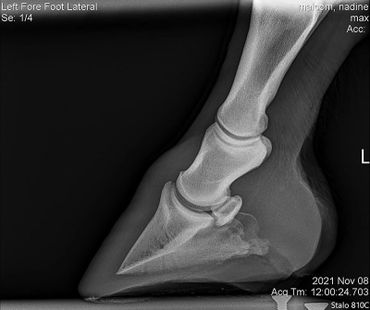

Due to an old injury Max was never sound on his front left. However, with Equioxx we have been able to keep him comfortable. He started going more lame on that foot so we had Dr. Johnson take a look at it. We did a nerve block and some x-rays to see what is going on. There are no significant changes to see so in the future on bad days we will just give him some banamine as well.